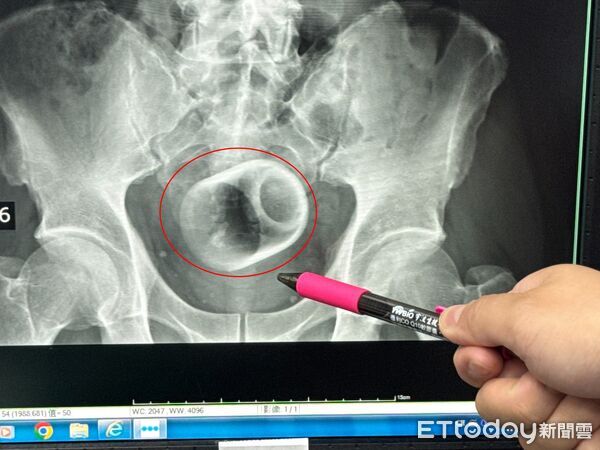

An X-ray examination soon revealed the culprit — a ceramic cup measuring 6cm in diameter and 8cm in height embedded deep within the man’s anus.